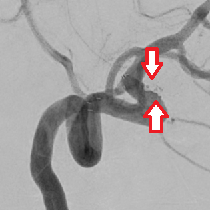

(下図)内頸動脈狭窄症に対して頸動脈ステント留置術を施行しました。良好な拡張が得られています。

頸動脈狭窄症、〇が狭窄している部分

頸動脈ステント留置術後